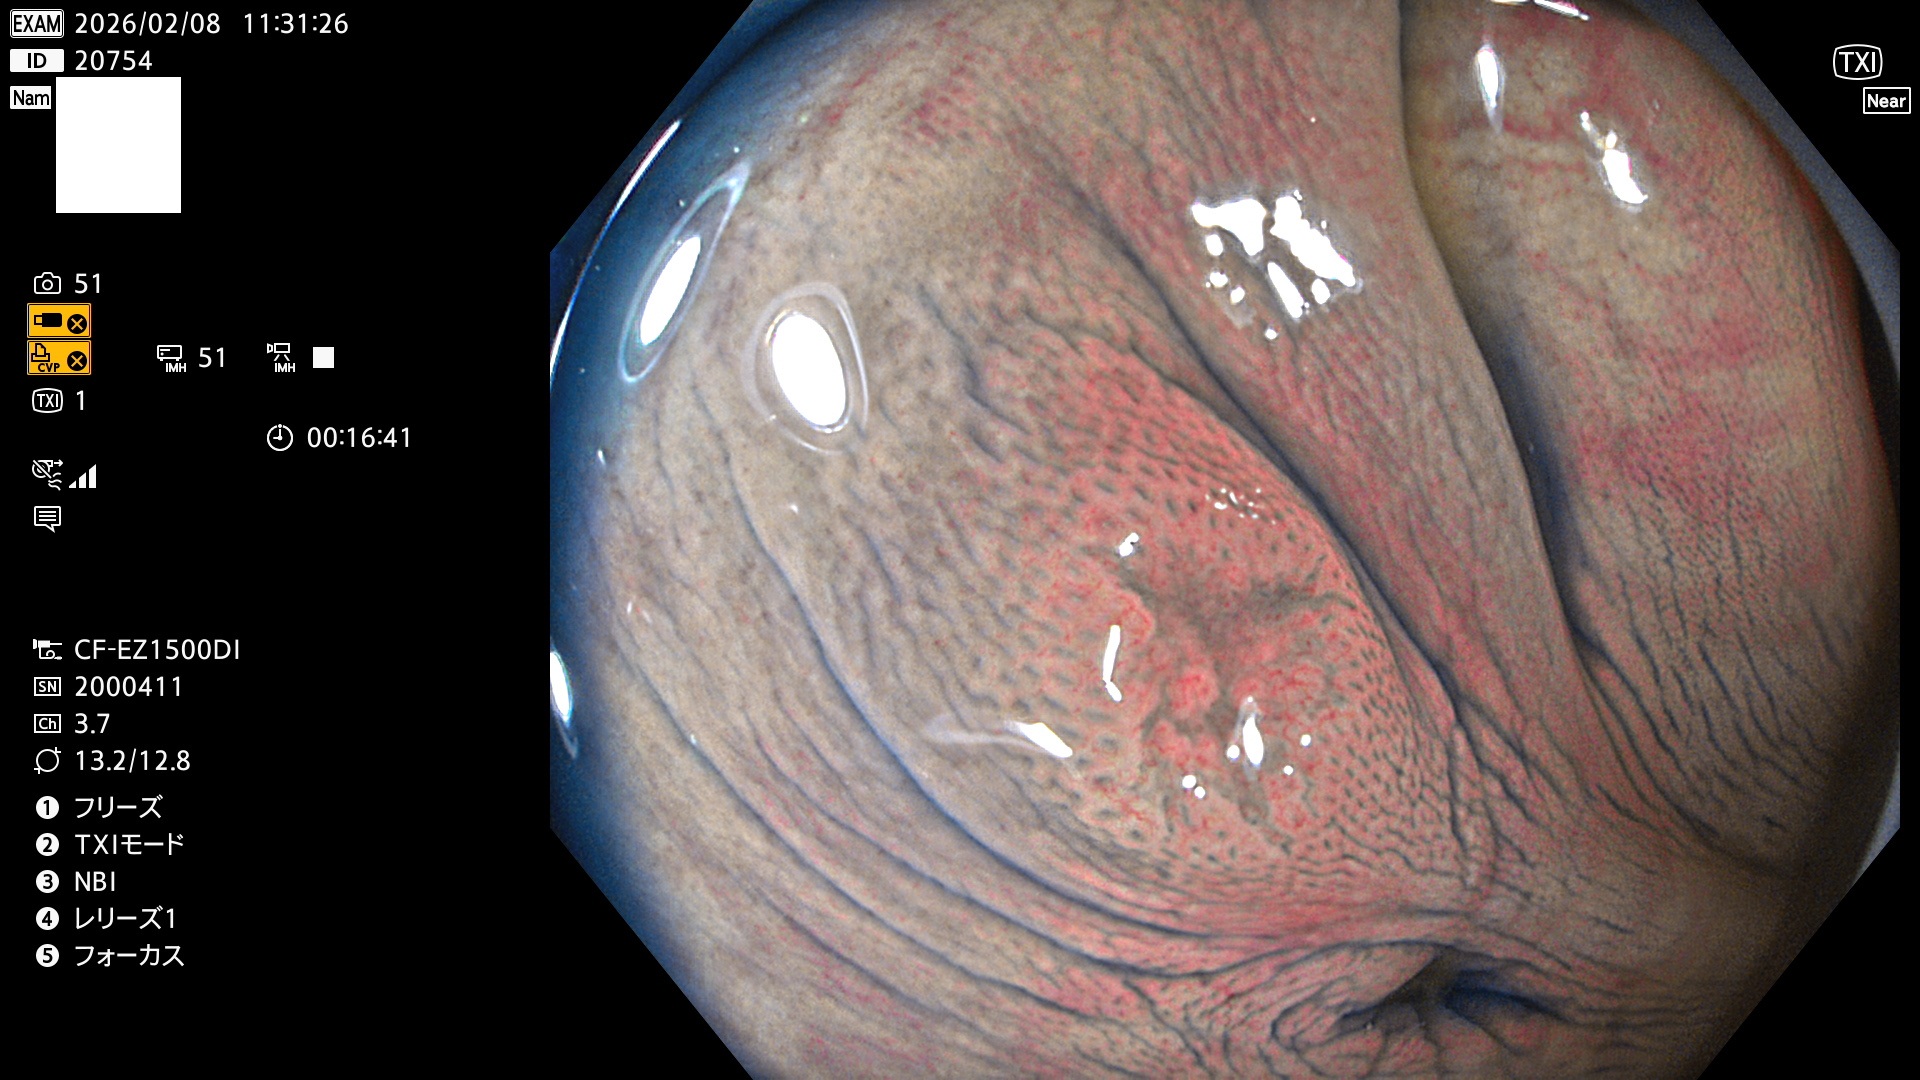

完全に平坦な物をUb、陥凹している物をUcと呼びます。Ubは認識が困難で、Ucはびらん(炎症)と紛らわしいために見落とされやすく、「内視鏡後・大腸癌」の原因になります。

専門的)Uc=De Novo癌? 内視鏡の解像度が低かった時代、このような説もありました。しかし今日の高精度内視鏡では良性の微小なUc型腺腫(APC遺伝子異常の腺腫)が日常的に見つかります。Ucこそが多段階発癌(Adenoma-Carcinoma Sequence)のMain Routeです。

毎週の検査(木・金・土・日)に発見されたUbとUc型・腺腫を、その週の日曜の夜にUPし1週間、提示します。

2026年2月5日〜2月8日の4日間(40件)9個 (Uc_ADR=9個/40人=23%)